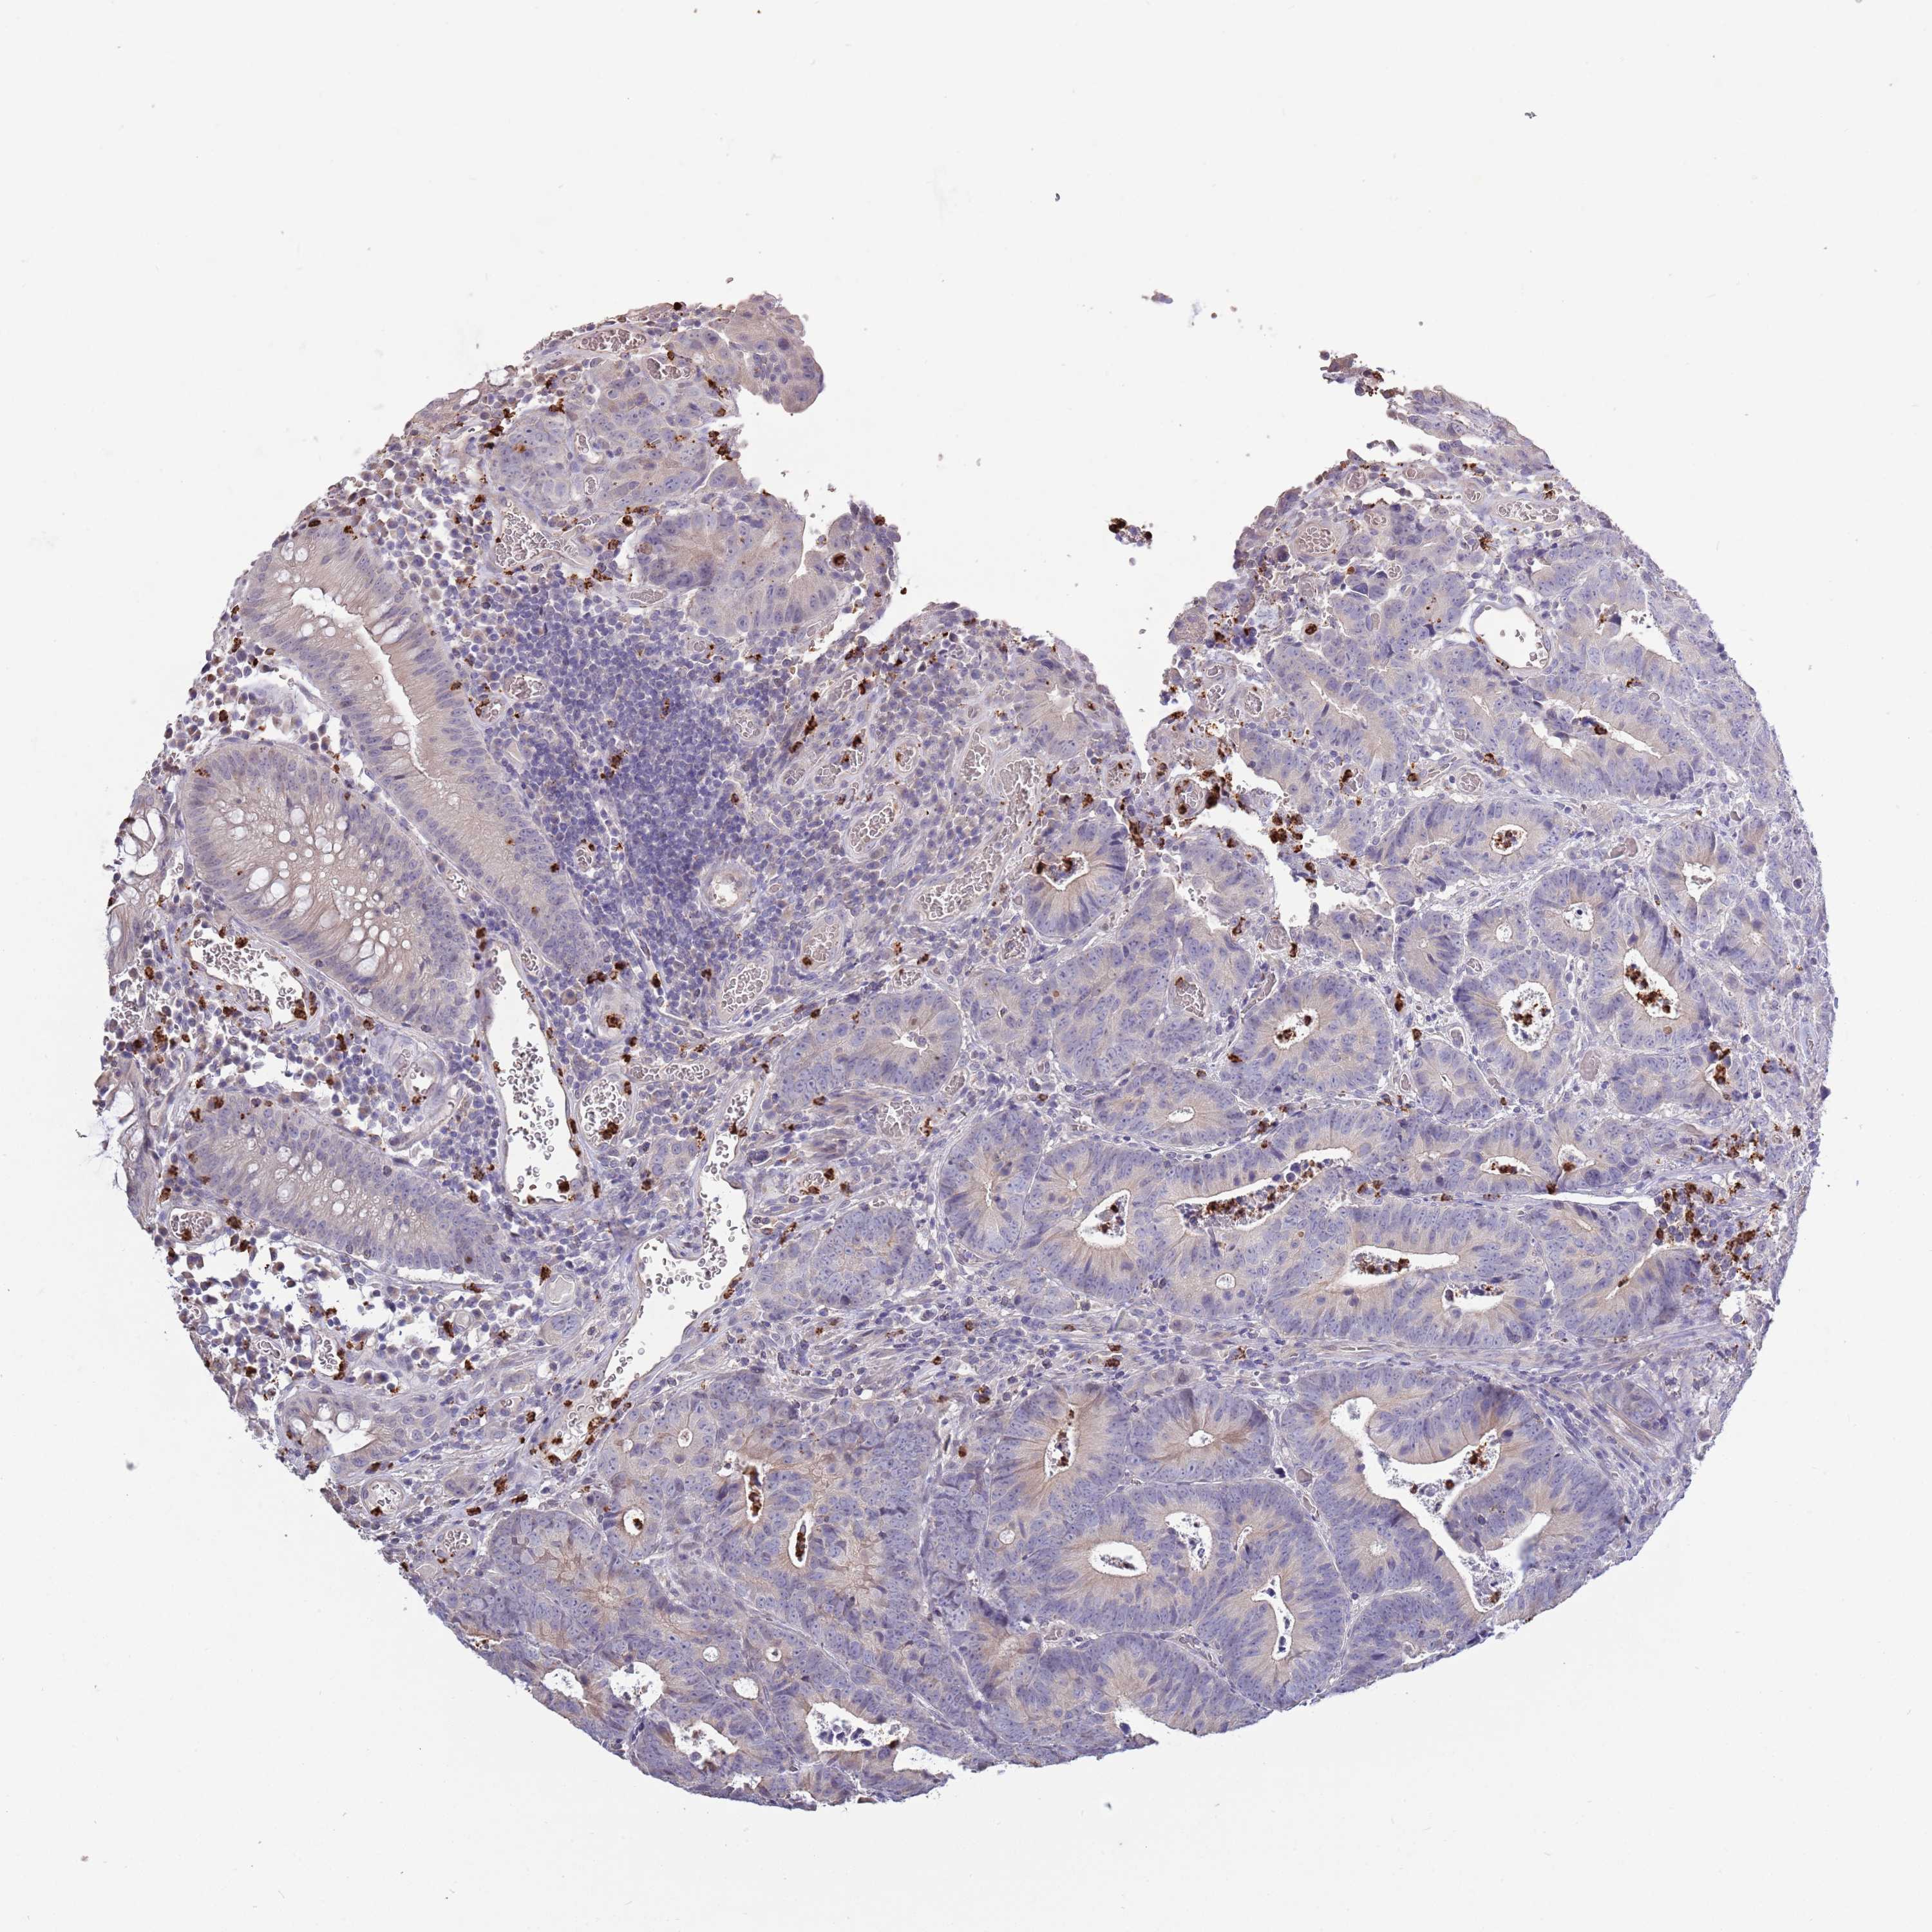

CANCER COLORECTAL CANCER Show tissue menu

Colorectal cancer

Colon adenocarcinoma